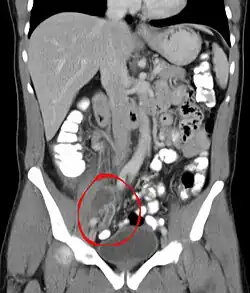

Die Diagnose „Perityphlitischer Abszess“ wird im Rahmen der ärztlichen Untersuchung gestellt. Bei der Sonografie (Ultraschall) kann der perityphlitische Abszess unerkannt bleiben. Eine sichere Diagnose ist mittels Computertomografie möglich.[5] Bei der Blutuntersuchung sind die Werte für Leukozyten und CRP deutlich erhöht, aber nicht, wenn der Abszess noch geschlossen ist.